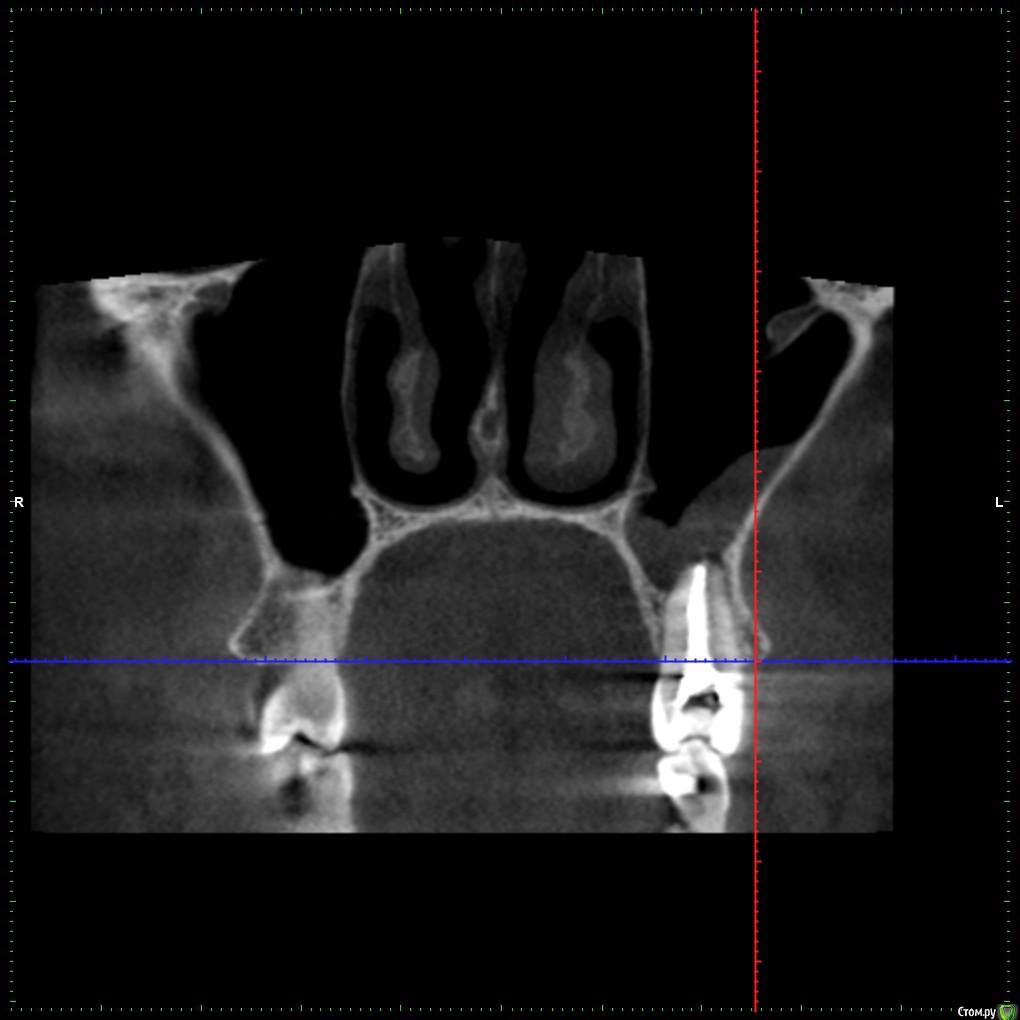

Freemind Опубликовано 13 июня, 2020 Поделиться Опубликовано 13 июня, 2020 Здравствуйте, уважаемые добрые врачи!Мне 32, мужеского полу. В начале мая обратился к своему стоматологу с жалобой на боль на холодное/горячее, точнее зуб реагировал на воду даже комнатной температуры (20-22 градуса), при надкусывании не болел. Мне казалось что это 5-й сверху слева. Он был два года назад лечен от пульпита, но сразу после лечения была странная симптоматика (хотя и пил ибупрофен 10 дней по рекомендации стоматолога): зуб не болел, не реагировал на холодное/горячее, но я его как-бы чувствовал при надкусывании/постукивании. Особого дискомфорта это не доставляло, поэтому забил и так и ходил. На приеме внешних признаков проблем не обнаружилось, сделали визиографию, увидели кисту, вскрыли зуб, три приема в течении 3- недель какие-то лечебные пасты(?) накладывали. Лучше становилось временами.Далее направил он меня на КТ. На снимках: киста оказалось над шестым, корни почти до пазух, гайморит (отчетливое воспаление, хотя из симтомов только периодические слабые головные боли в области левого виска и скудные желтовато-зеленые выделения по утрам из носа при сморкании). Этот шестой был лечен от пульпита лет 6-7 назад у другого стоматолога. Вскрыл его, обнаружил один не леченый канал (Сам я этого не вижу на КТ). Лекарство. К второму приему по 6-му зубу вроде стало получше,- на воду комнатной температуры точно перестало болеть, на откровенно холодное чаще реагирует, чем нет. Направил он меня к ЛОРу, который прописал пока назонекс, предложил варианты: 1) либо лечить зуб, смотреть динамику и далее толи 1.1.делать операцию на пазухе, толи 1.2. удалять зуб, опять смотреть. 2) сразу удалять, смотреть динамику. На сейчас: уже три раза лечебная паста(?) на 6-й. Периодически головные боли несильные, периодически реагирует на холодное и чуть поднывает. А бывает день вообще не замечаю никакого дискомфорта. Вопросы:1. На снимке киста?, есть ли перфорация? - мне кажется по снимку видно, что при лечении одного из корней (6-7 лет назад) пробита пазуха - может гайморит от перфорации, а не от кисты?.2. Почему мне субъективно кажется, что болевые ощущения когда они есть идут от 5-го, хотя киста над 6-м? Даже когда нет никаких болей, 5-й все проявляет эту странность - "как бы чувствую" его в корню (при постукивании ощущение очень отдаленно сродни щекотки).3. Стоит ли уже залечивать на постоянную эти зубы? или удалять 6-й? или сделать снова КТ сейчас? Может эта киста вообще рассосаться? Еще одно уточнение, не уверен, что относится к теме. В конце февраля было 2 дня дико плохое самочувствие - сначала только сильная ломота во всем теле, затем прибавилась температура 38. Еще пару тройку раз такое повторялось в слабой форме без температуры до середины мая. Т.е. это точно не ОРВИ была. Обследоваться начал - флюорография чистая., анализы на ВИЧ, гепатиты не успел - больницы на карантин закрылись (хотя образ жизни сильно далек от факторов риска этих инфекций). В любом случае исчезновение этих приступов ломоты совпало с началом лечения зубов - хз совпадение нет ли? С уважением, Александр. Извините за такой опус, просто что-то боязно становиться за свою тушку. P/S: вся КТ здесь https://drive.google.com/file/d/1gya4SSUk5vu8DrihvHP74CF-IKWj9XCk/view?usp=sharing. Ссылка на комментарий

St. Опубликовано 14 июня, 2020 Поделиться Опубликовано 14 июня, 2020 Добрый день. 1. На снимке киста? На снимке периодонтит, по простонародному "киста". И плюс реакция слизистой оболочки гайморовой пазухи на него. есть ли перфорация? Перфорация чего? в зубе - не видно мне кажется по снимку видно, что при лечении одного из корней (6-7 лет назад) пробита пазуха - может гайморит от перфорации, а не от кисты?. Есть немного выведенного материала, это не критично. 2. Почему мне субъективно кажется, что болевые ощущения когда они есть идут от 5-го, хотя киста над 6-м? Покажите срезы в области 5 3. Стоит ли уже залечивать на постоянную эти зубы? Имеет смысл попробовать и посмотреть на динамику. через 6 мес сделать контрольные снимки. сделать снова КТ сейчас? Раньше 6 мес после постоянной пломбировки каналов не имеет смысла Может эта киста вообще рассосаться? Да 2 Ссылка на комментарий

Freemind Опубликовано 16 июня, 2020 Автор Поделиться Опубликовано 16 июня, 2020 Огромное Вам спасибо! Покажите срезы в области 5 Ссылка на комментарий

St. Опубликовано 16 июня, 2020 Поделиться Опубликовано 16 июня, 2020 Я бы начинала перелечивание с 6, если дискомфорт пройдет, то ок. Если нет, то перелечивать и 5 ( по кт канал заполнен на всю длину вполне плотно, но кость за пределами корня неоднозначная..) Ссылка на комментарий